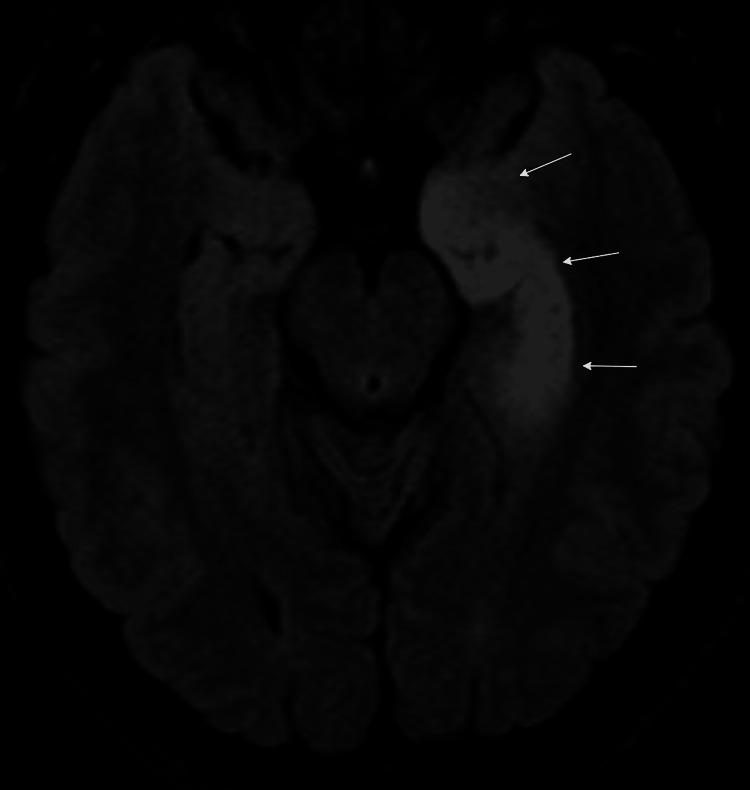

Glutamic acid decarboxylase 65 (GAD65) antibody-associated autoimmune encephalitis is a rare neurological disorder characterized by cognitive impairment, seizures, and psychiatric manifestations. Long-term outcomes and management strategies for this condition remain poorly documented in the medical literature. We present a nine-year follow-up of a young woman with GAD65 antibody-positive autoimmune limbic encephalitis who achieved complete clinical remission following aggressive immunomodulatory therapy. The patient, initially treated with rituximab, intravenous immunoglobulin (IVIG), and mycophenolate, successfully discontinued all immunosuppressive medications except hydroxychloroquine. She remains clinically asymptomatic with no recurrence of olfactory hallucinations or other neurological deficits, despite persistently elevated serum GAD65 antibody levels and persistent signal abnormalities on brain imaging. This case highlights the potential for favorable long-term outcomes in GAD65 antibody-associated encephalitis with appropriate immunotherapy and provides insights into maintenance therapy and medication withdrawal strategies for patients planning pregnancy.

摘要

谷氨酸脱羧酶65(GAD65)抗体相关的自身免疫性脑炎是一种罕见的神经系统疾病,其特征为认知障碍、癫痫发作和精神症状。关于这种疾病的长期预后和管理策略在医学文献中仍记载不足。我们报告了一名患有GAD65抗体阳性自身免疫性边缘叶脑炎的年轻女性的九年随访情况,该患者在积极的免疫调节治疗后实现了完全临床缓解。该患者最初接受了利妥昔单抗、静脉注射免疫球蛋白(IVIG)和霉酚酸酯治疗,除羟氯喹外成功停用了所有免疫抑制药物。尽管血清GAD65抗体水平持续升高且脑成像显示持续的信号异常,但她仍无临床症状,嗅觉幻觉或其他神经功能缺损也未复发。该病例突出了通过适当免疫治疗,GAD65抗体相关脑炎获得良好长期预后的可能性,并为计划怀孕的患者的维持治疗和停药策略提供了见解。